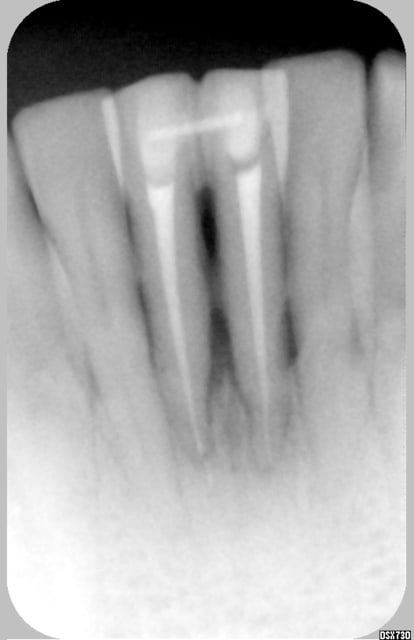

athos

15/04/2006 à 13h34

suivi de cas